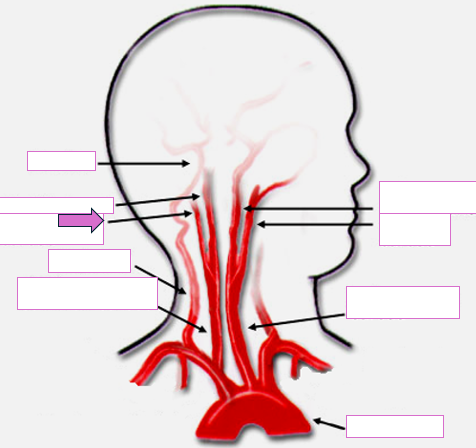

Based on the indicated area, identify this vessel

Basilar

Right internal carotid

Right external carotid

Vertebral

Right common carotid

Left internal carotid

Left external carotid

Left common carotid

Aortic arch